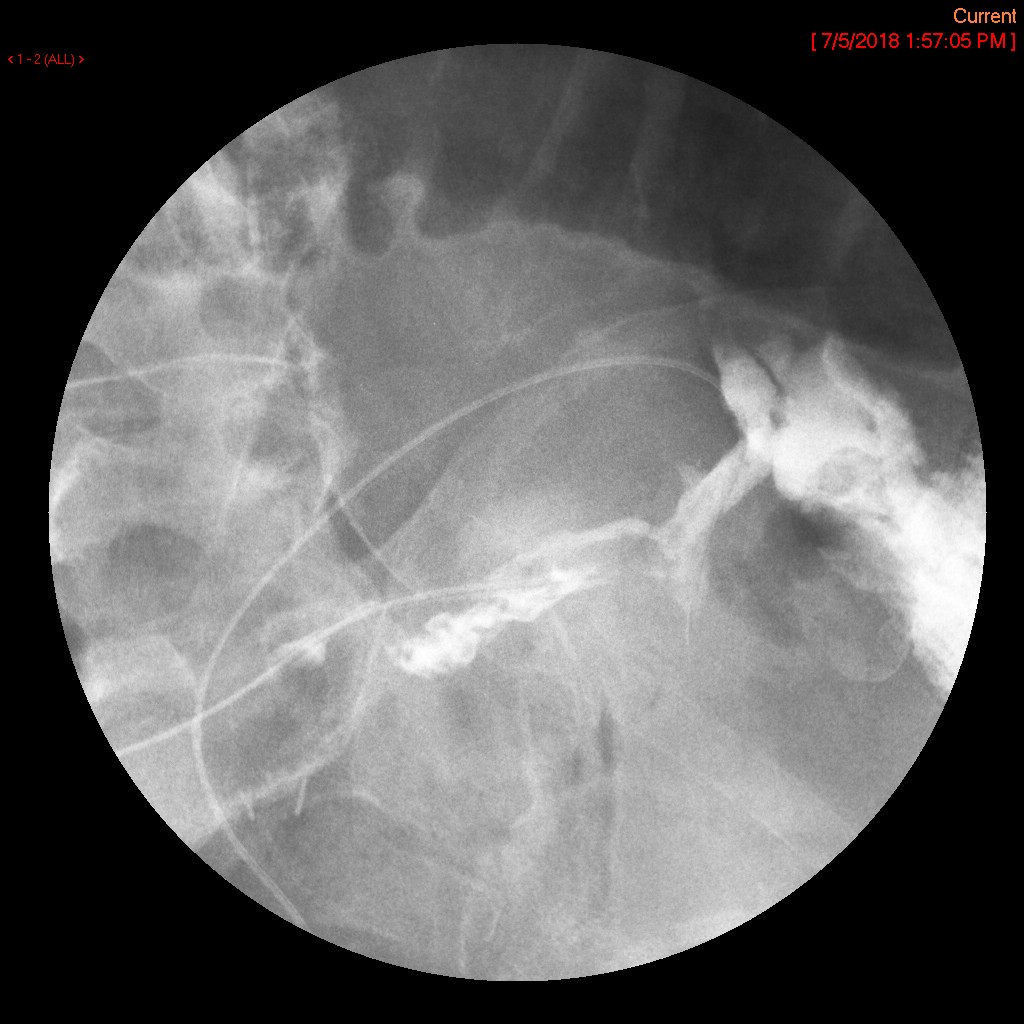

- The gynecologist will begin injecting contrast material into the uterus. Obtain images periodically throughout the procedure (usually at the direction of the gynecologist). The images should include the uterine cavity filled with contrast material, bilateral fallopian tubes filled with contrast material, and spillage and dispersion of contrast material into the peritoneal cavity (image 1) (image 2) (image 3) (image 4) (image 5).